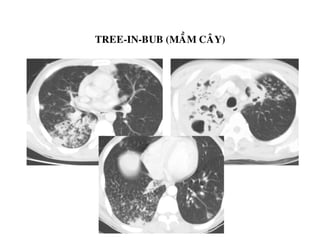

-Tree-in-bud (maàm caây)

-Noát phaân boá ngaãu nhieân

-Do u, vieâm, buïi phoåi…

TREE-IN-BUB (MAÀM CAÂY)

DAÏNG NOÁT